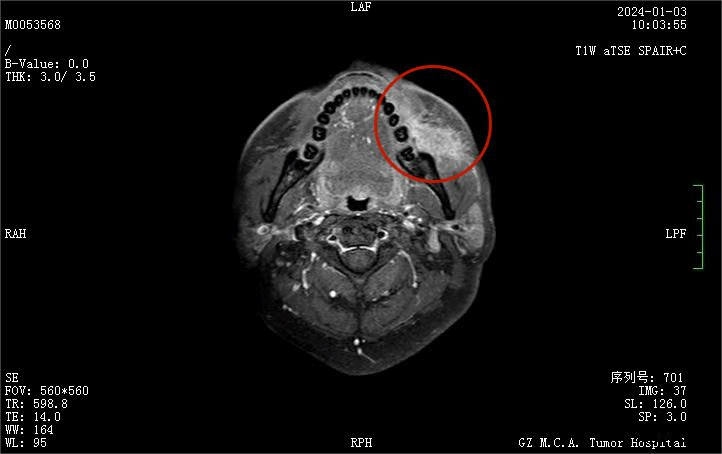

磁共振影像显示左颊部团块状肿物大小达48×39×52mm(比高尔夫球大)

新辅助治疗后的磁共振影像(肿物缩小至硬币大小,累及程度减轻,左侧颊肌、咬肌强化影较前减轻)